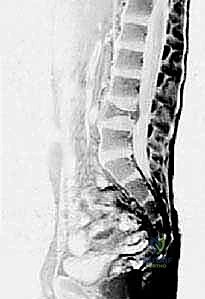

صورة الرنين المغناطيسي (MRI) توضح بوضوح السائل المتجانس داخل كيس العظم أحادي الغرفة، مما يساعد الأستاذ الدكتور محمد هطيف في استبعاد الأورام الصلبة.

التصوير بالرنين المغناطيسي (MRI):

- ضروري لتقييم محتوى الكيس وتأثيره على الأنسجة الرخوة المحيطة وصفيحة النمو.

في الـ ABC، يُظهر الرنين المغناطيسي علامة كلاسيكية تُعرف بـ "مستويات السائل-السائل" (Fluid-Fluid Levels)، والتي تنتج عن ترسب خلايا الدم الحمراء وانفصالها عن مصل الدم داخل تجاويف الكيس.